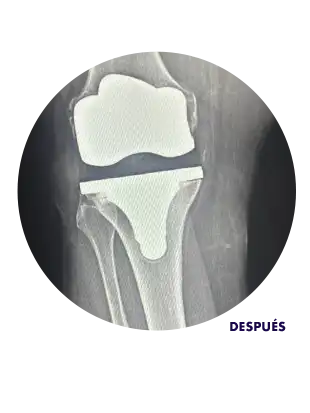

Radiografía mostrando rodilla después de reemplazo de rodilla

El reemplazo de rodilla, también conocido como artroplastia total de rodilla, consiste en sustituir las superficies articulares dañadas de la rodilla por una prótesis hecha de metal, cerámica y polímero de alta durabilidad.